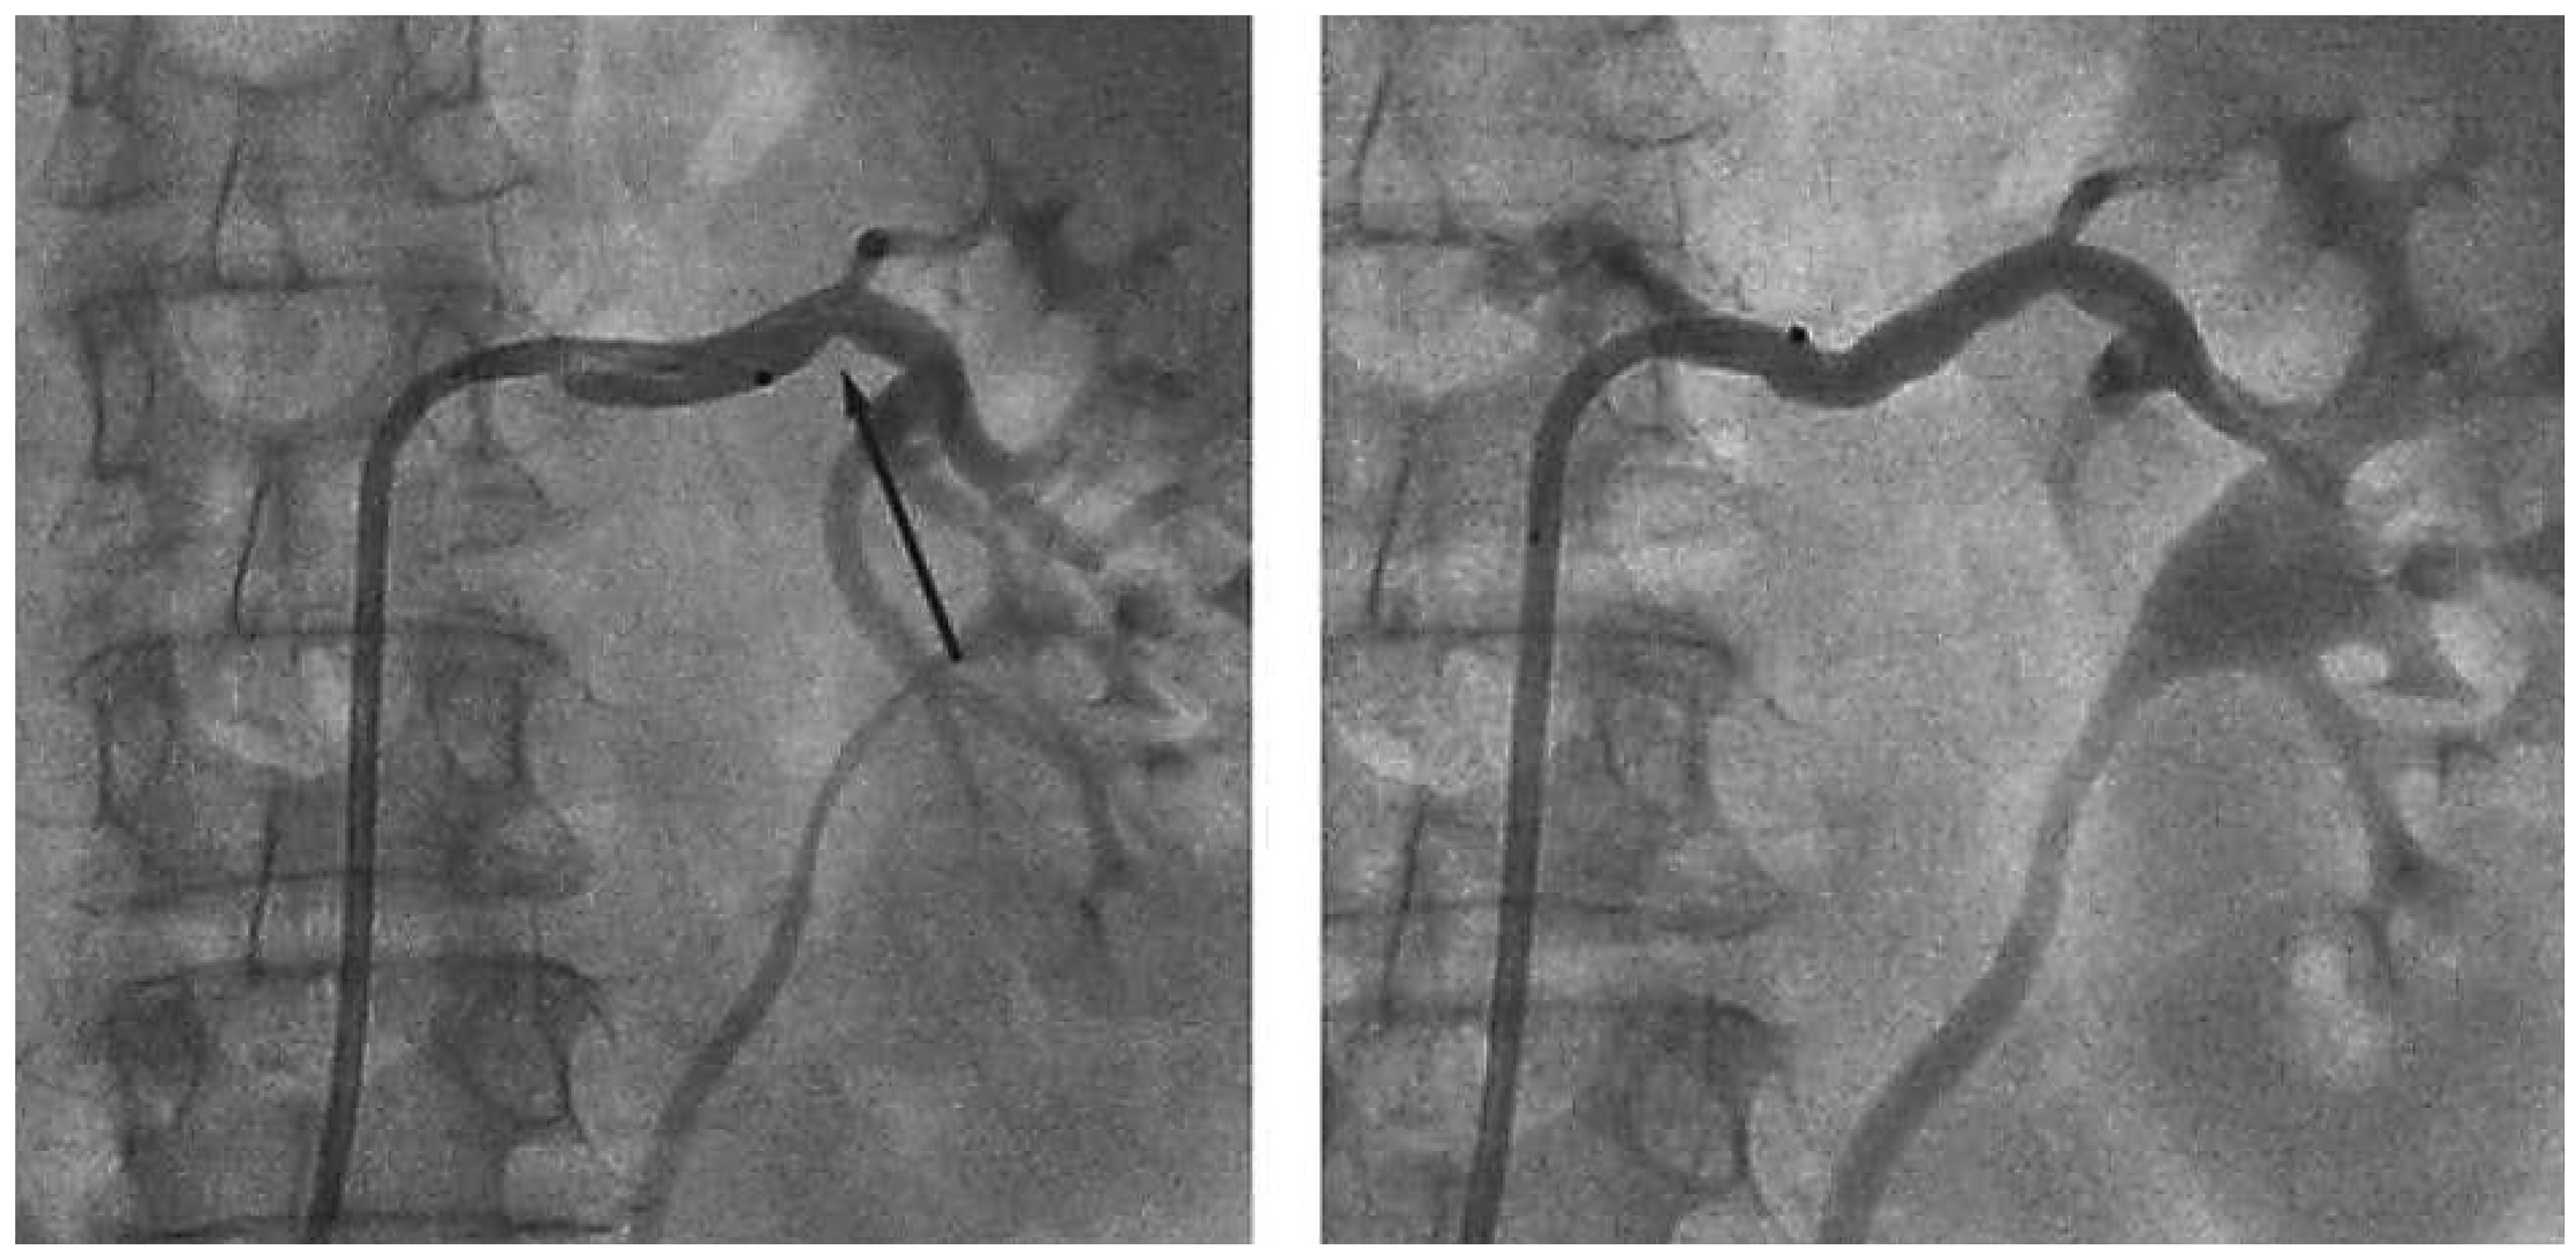

- Die Nierennervenablation mit dem Symplicity-Katheter funktioniert nicht. In der Tat gibt es zahlreiche neuere Systeme, so Ablationskörbe mit vier gleichzeitig anliegenden Ablationselektroden, Ablationsballone mit bipolarem Radiofrequenzablationssystem, Ultraschallkatheter und auch zuletzt Alkohol-Injektionssysteme. Ob die neueren Systeme besser wirken als das erste SymplicitySystem, sollte in zukünftigen Studien untersucht werden.

- Interventionen wurden nicht sachgemäss durchgeführt. In der Tat haben 111 Operators in 88 Zentren bei 364 Patienten Nierennervenablationen durchgeführt. Damit haben die allermeisten Operators innerhalb der Studie zum ersten Mal einen, zwei oder drei solcher Eingriffe durchgeführt. Wenn sich der Eingriff durch erfahrene Interventionalisten auch in der Regel einfach gestaltet, besteht dennoch eine Lernkurve, insbesondere bei der spiraligen Applikation der Ablationspunkte, welche in dieser Form zwingend sind, um eine wirksame Nervenblockade zu erreichen.